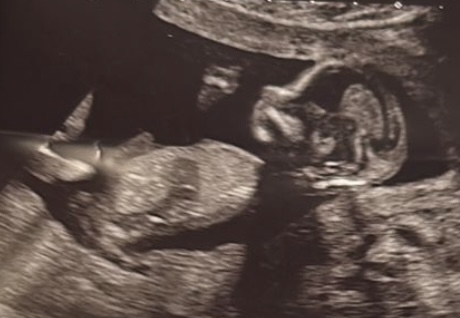

Arkadaşlar merhaba benim 14 haftalık ultrason görüntüm nub teorısıne göre yorum yapabılır mısınız şimdiden teşekkürler

Hayatım selamlmar net olmamakla birlikte erkek diyebilirim daha yakın çekim resim atabilir misin tek birini atsan yeterli yani kare kare var ya birini yakın çekim atar mısın tşk.